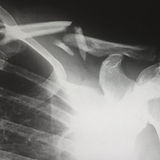

手臂抬高或外展過程在60-120度會有疼痛。

摸對側肩膀或稍息動作會引起疼痛。